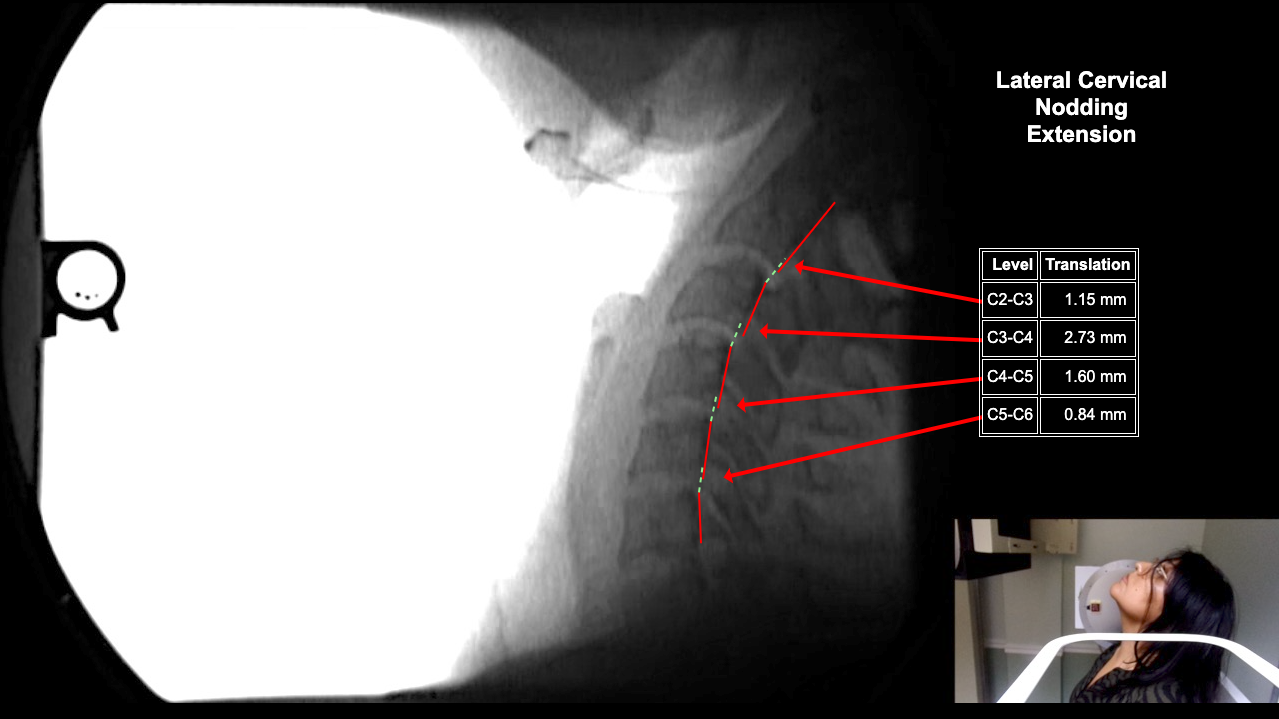

Home > Ana Cespedes